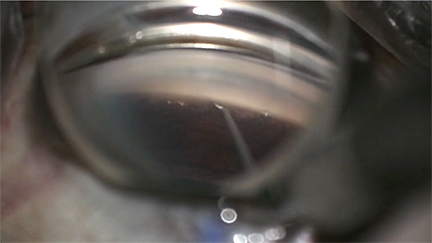

A 2.4 mm main wound was made for the Allo-Flo. A Provis cannula was used to create a cyclodialysis by gently peeling the circular and longitudinal fibers of the ciliary body off of the back wall of Schlemm. Viscoelastic can be directly injected into the cyclodialysis cleft while creating it to both widen it and to tamponade all bleeding. Despite this patient’s aspirin use, the very heavy Healon5 keeps the blood at bay and the view very clear.

The Allo-Flo scleral spacer enters the eye and is docked into the cyclodialysis cleft that was previously created. It’s pushed forward until it’s engaged in the cyclodialysis cleft, taking care not to overimplant it. The white button on the inserter is pushed down and pulled back to retract the sheath and leave the Allo-Flo in place.

A second Allo-Flo scleral spacer is inserted in the same cyclodialysis cleft, approximately 1 spacer width away from the first Allo-Flo. Again, the white button on the inserter is pushed down and pulled back to retract the sheath from the spacer and leave the spacer in place. The second spacer was deployed a little too deep, so MST forceps were used to pull it back and nudge it slightly to the side. Healon was injected into the gap in between the 2 spacers to ensure there was adequate space between them. Both wounds were sutured out of an abundance of caution and some, but not all, of the viscoelastic was rinsed out of the AC. Some viscoelastic was purposely left in the AC to dampen the amplitude of IOP drop and reduce hypothetical reflux bleeding from the goniotomy site. The second Allo-Flo had retracted somewhat into the AC, so it was nudged deeper into the cyclodialysis cleft. The wounds were hydrated and confirmed to be watertight, and the case was complete.